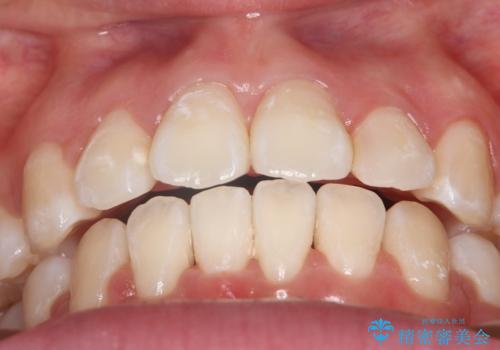

抜歯矯正をして口元を下げたことで、口元が下がりEラインが大変綺麗になりました。

矯正期間も1年9ヶ月と比較的短期間で終了することができました。